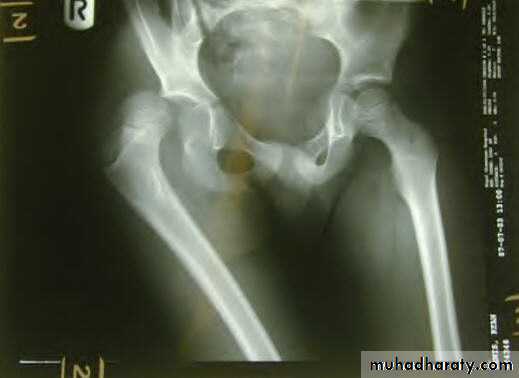

X-ray : AP view : the femoral head is seen out of its socket and above the acetabulum . There may be associated fracture in the femoral head or in the rim of the acetabulum .

Posterior hip dislocation

It is the commonest typeMechanism of injury :

It occurs in road traffic accident when someone seated in truck or car is thrown foreword striking the knee against the dashboard . The femur is thrust backward and the femoral head is forced out of its socket . Often a piece of bone of the acetabulum is sheared off making it a fracture – dislocation

the leg is short ,adducted , internally rotated and slightly flexed .